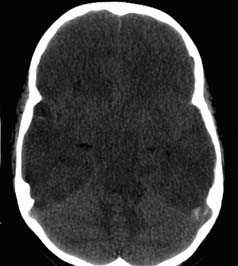

КТ позволяет последовательно изучить мягкие ткани головы, кости черепа, вещество мозга, эпидуральные, субдуральные, субарахноидальные пространства, цистерны основания и желудочки мозга:

- выявить наличие внутричерепной гематомы (её характер, локализацию, размеры),

- выявить наличие очага ушиба головного мозга (его локализацию, размеры, характер, наличие геморрагического компонента),

- выявить наличие диффузного или перифокального отека и его степени,

- выявить субарахноидальное кровоизлияние,